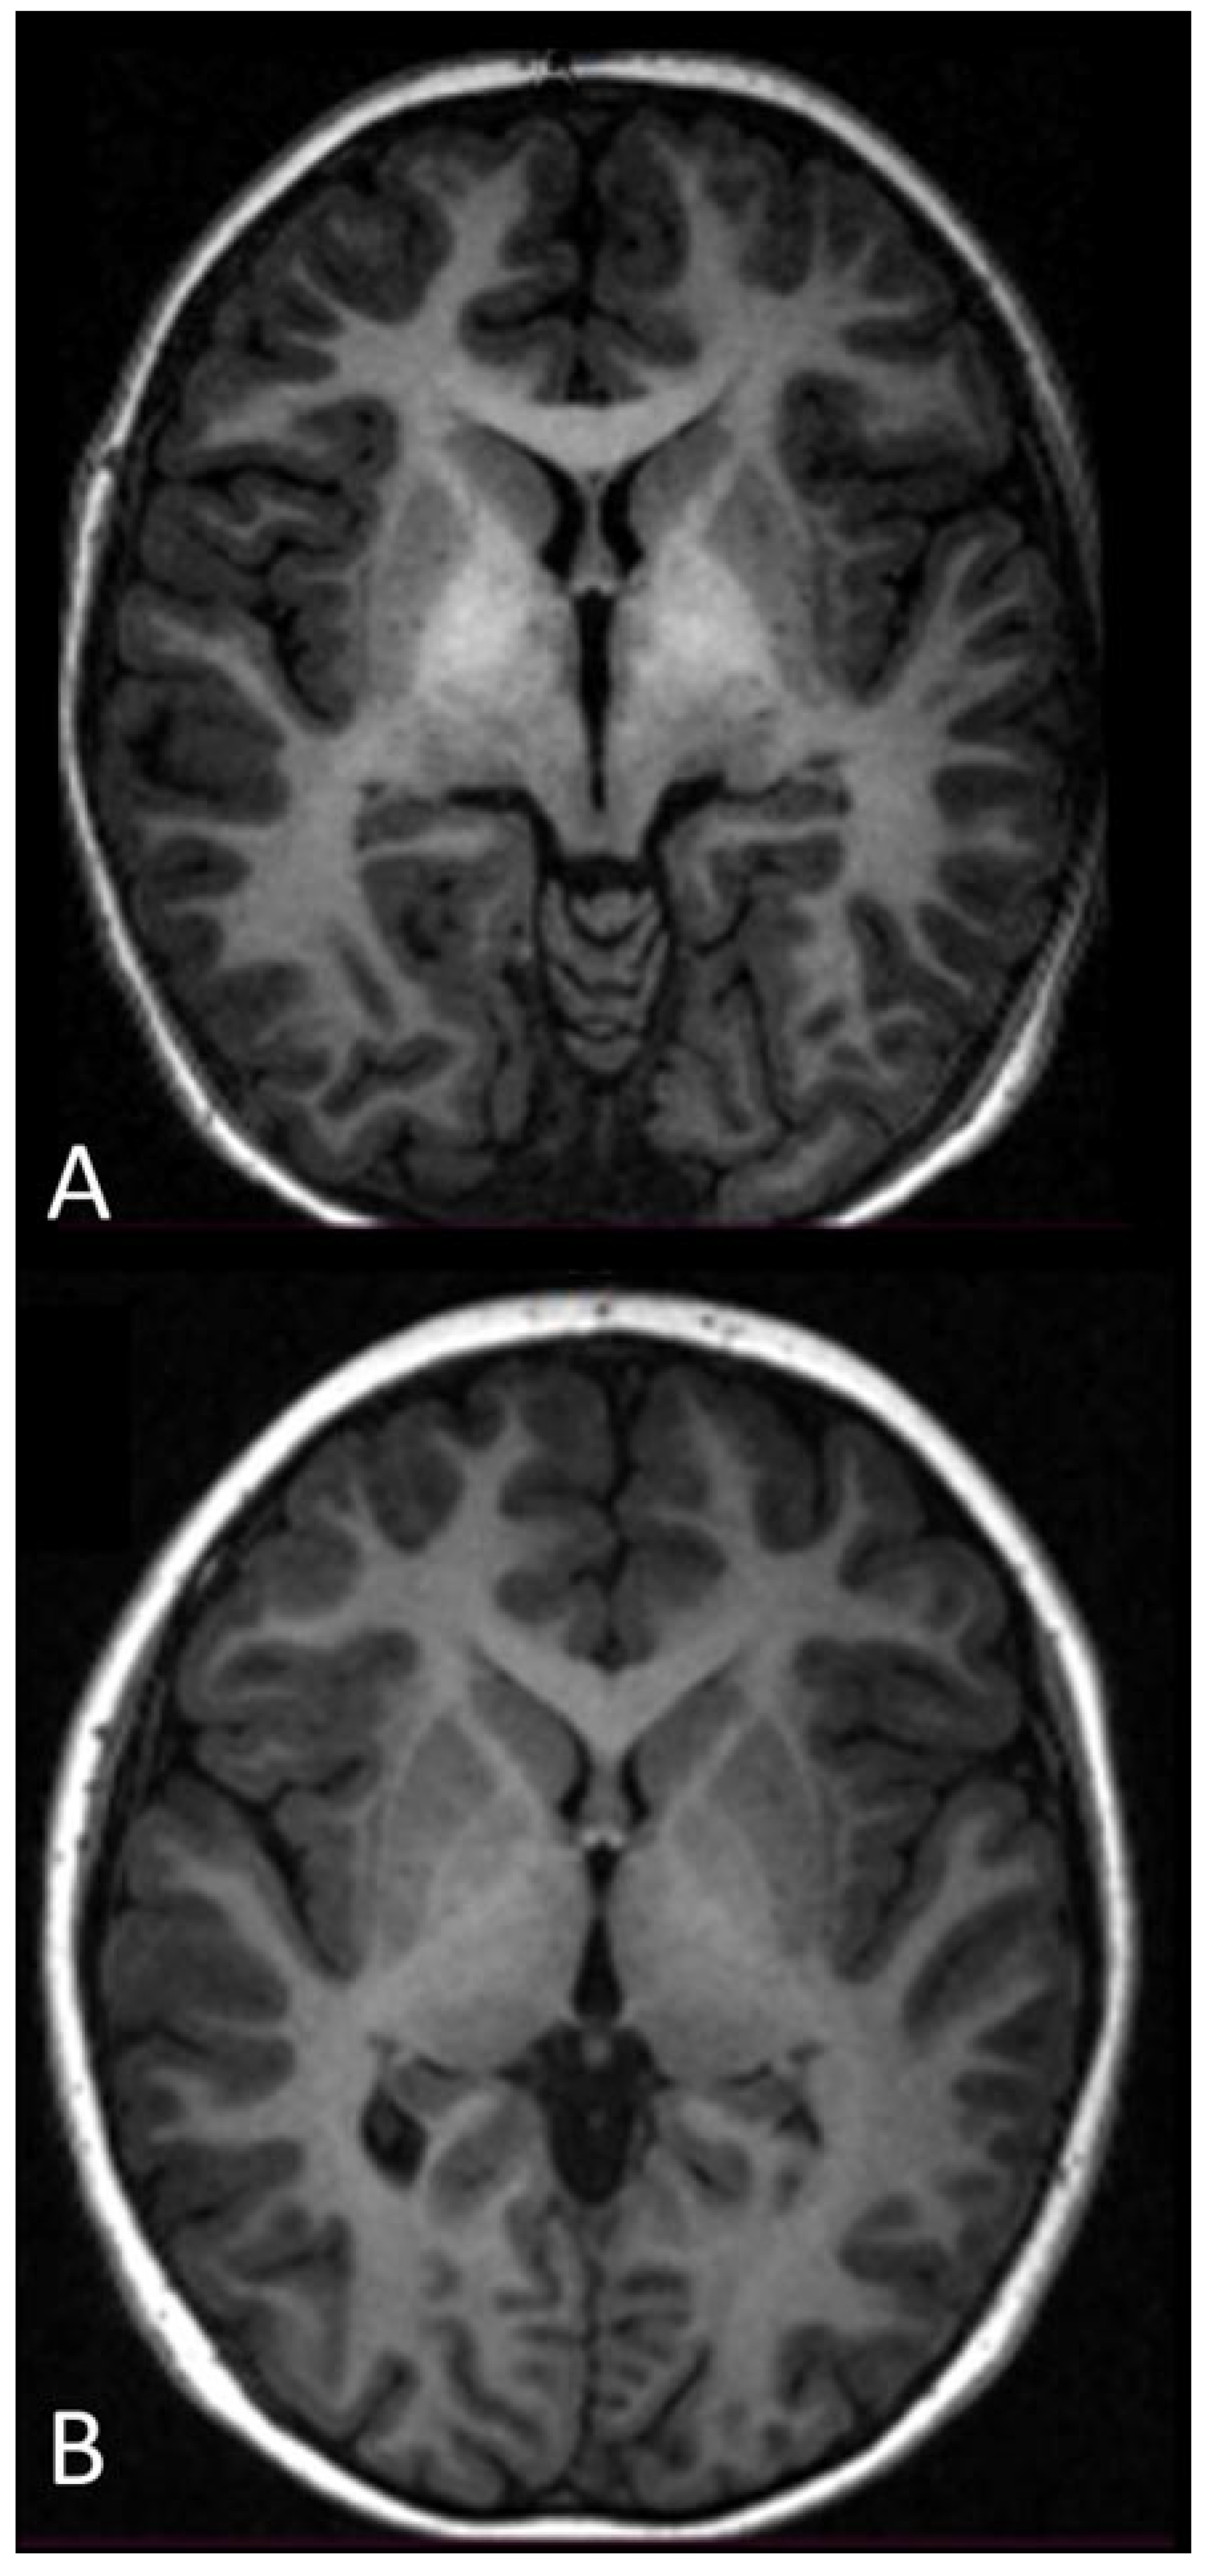

- Though the phenomenon was slower, MRI evidenced the disappearance of the hyperintensity of the globus pallidus on T1-weighted sequences (in two cases that had follow-up >1 year). This needs further studying.